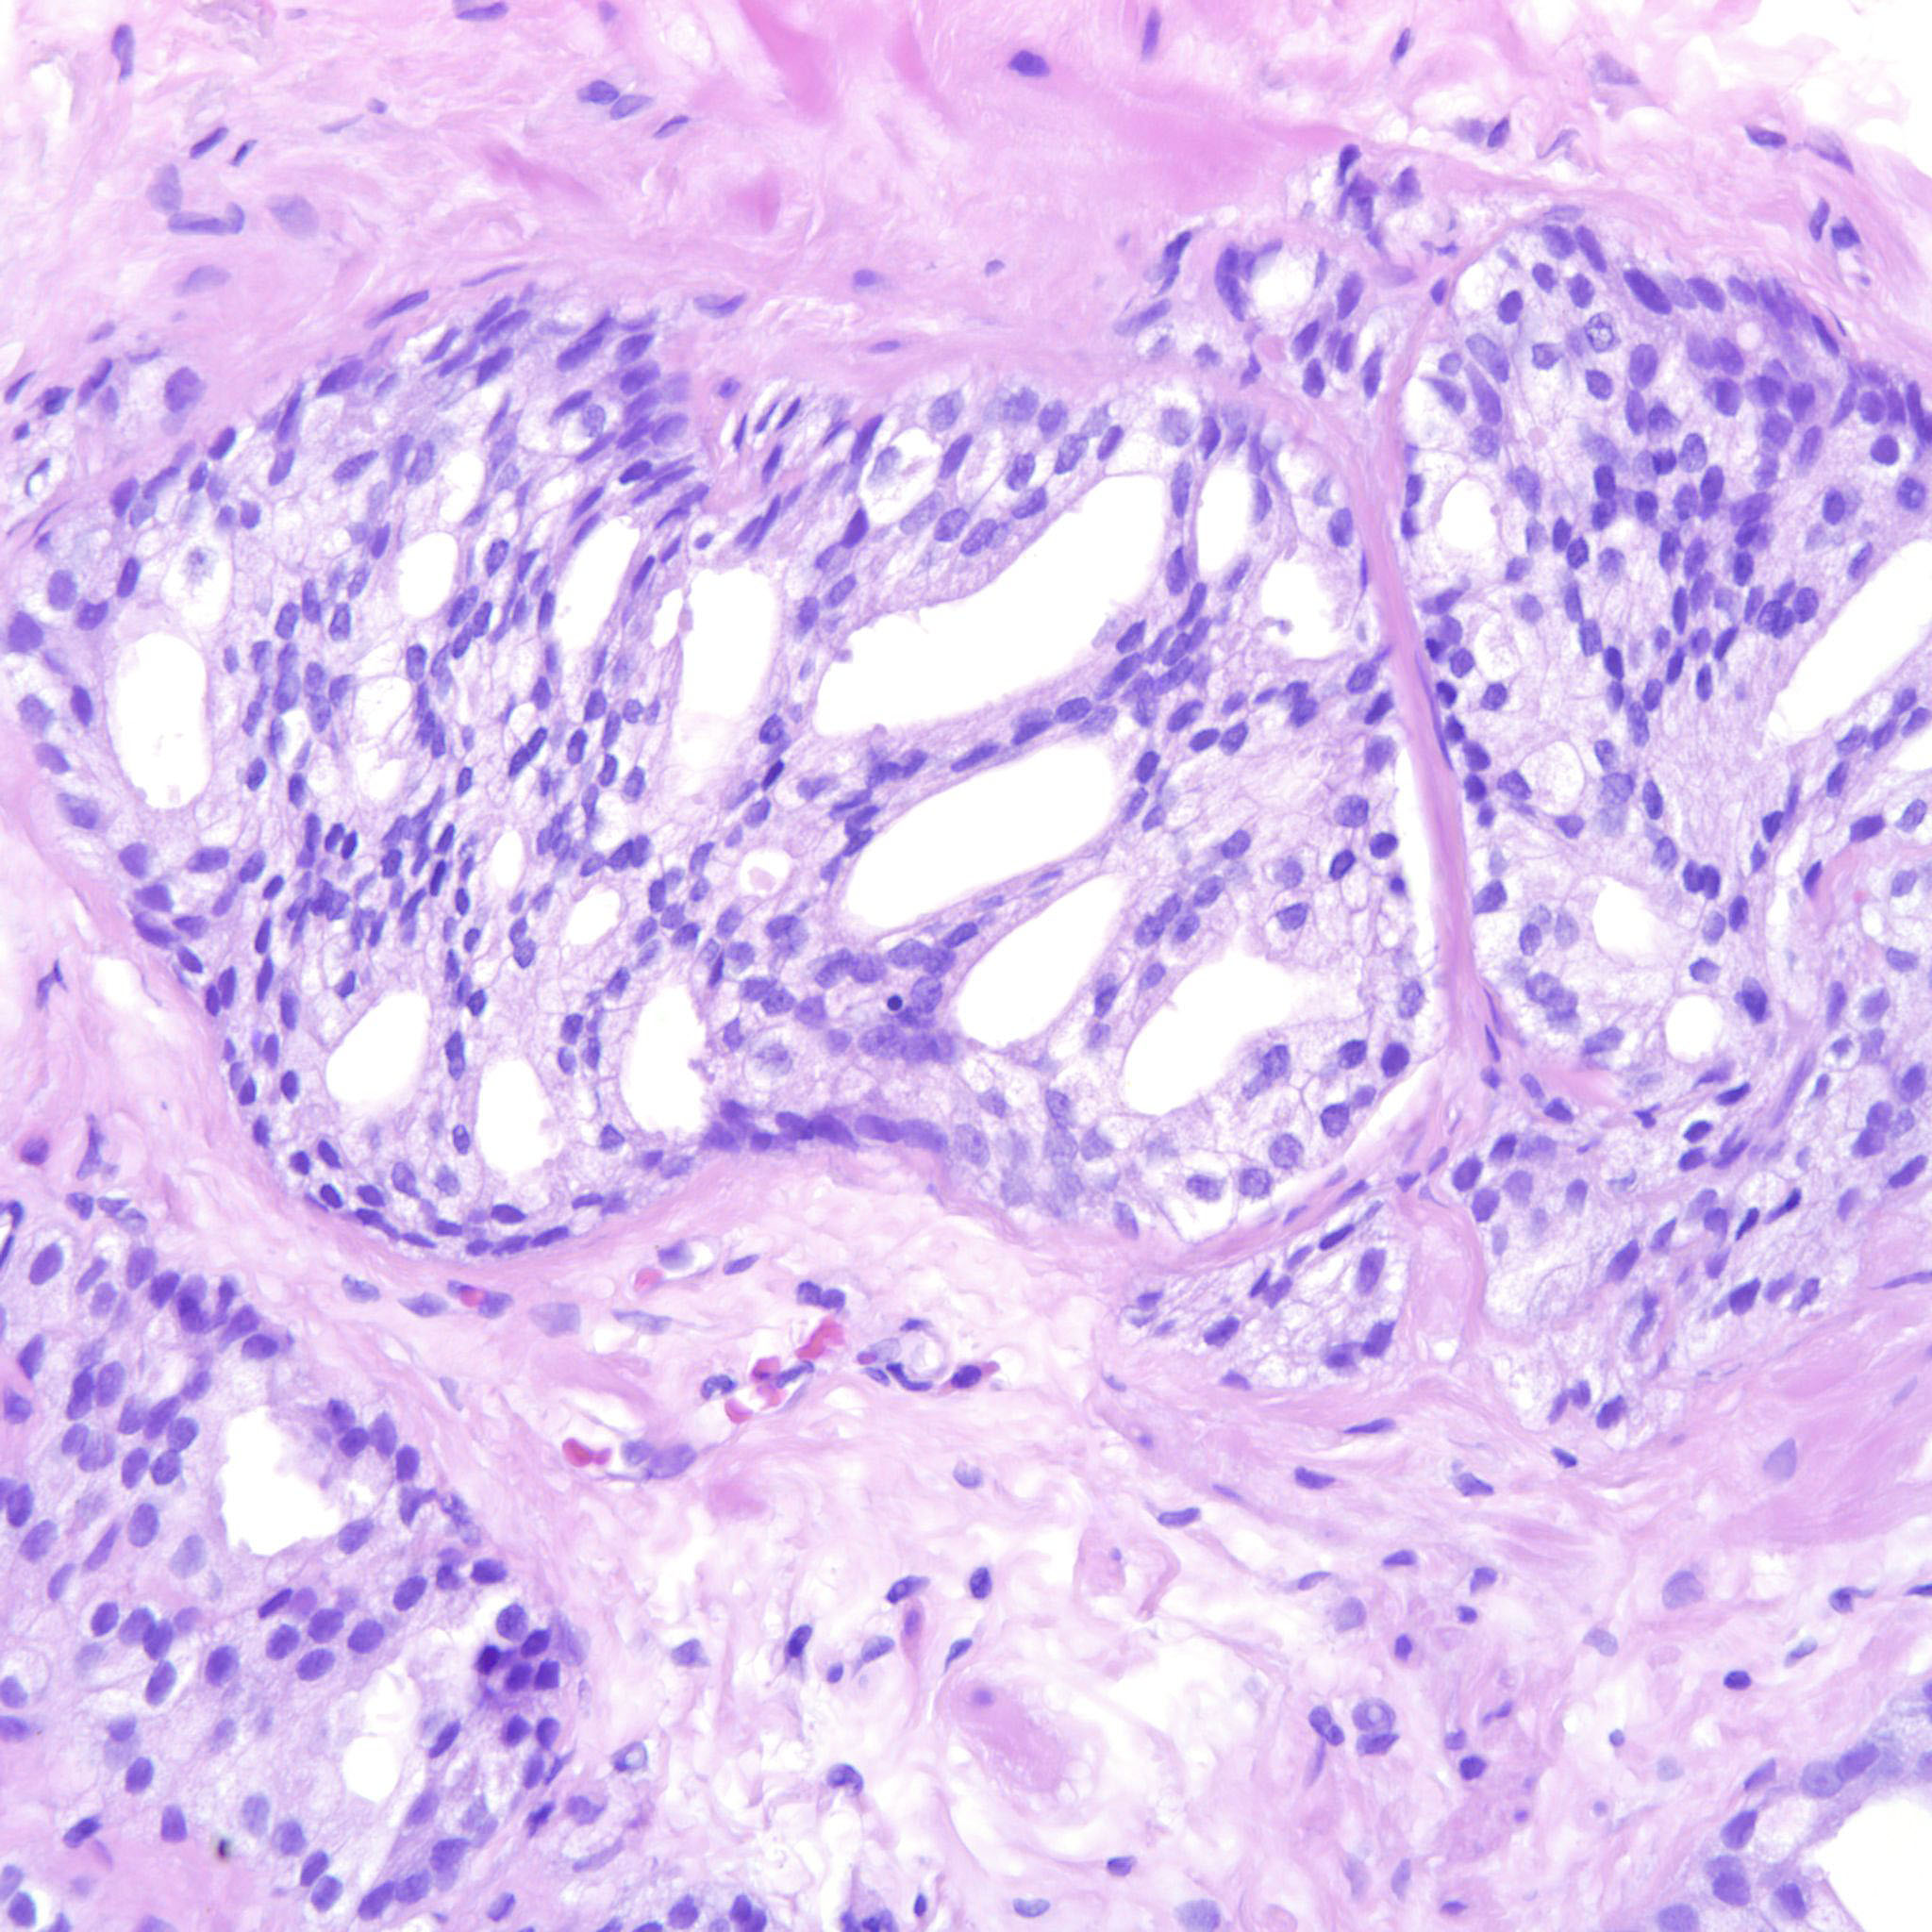

Prostate cancer grading

Case ID: 275